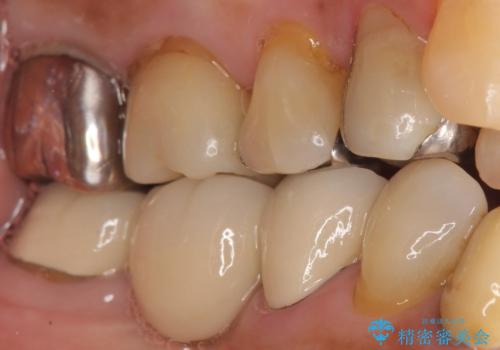

銀歯を外した後う蝕を丁寧に除去し、適合の良い仮歯に変えたところ、歯ブラシをあてた時の痛みがなくなったとのことでした。

オールセラミッククラウンの審美的な仕上がりと自然な咬み心地に喜んで頂けました。